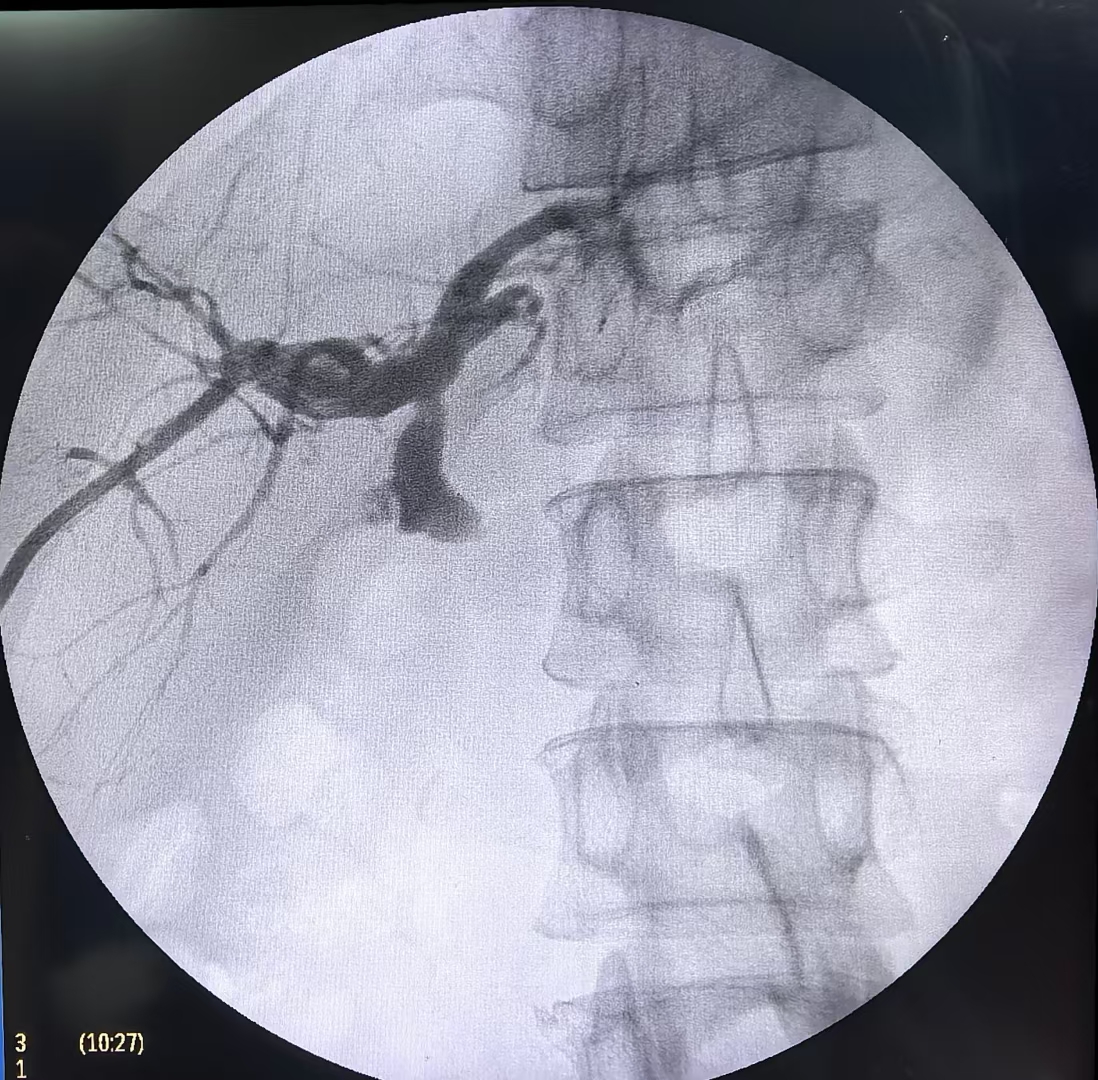

孙昊、李宇教授团队采用的磁疏通技术,创新性融合磁力学原理与微创操作,通过经皮肝穿刺胆道引流术(PTCD)和ERCP路径,将钕铁硼复合永磁体制成的子母磁体,分别送至梗阻胆道的近端与远端。异极磁力瞬间吸附实现组织“秒级吻合”,使梗阻部位组织受压坏死脱落,周围健康组织通过粘连修复形成光滑吻合口,最终实现胆道再通。整个过程无需传统针线缝合,手术时间缩短至传统术式的1/3,且对患者创伤极小。术后患者生命体征平稳,胆道梗阻症状迅速缓解,肝功能指标逐步恢复正常。